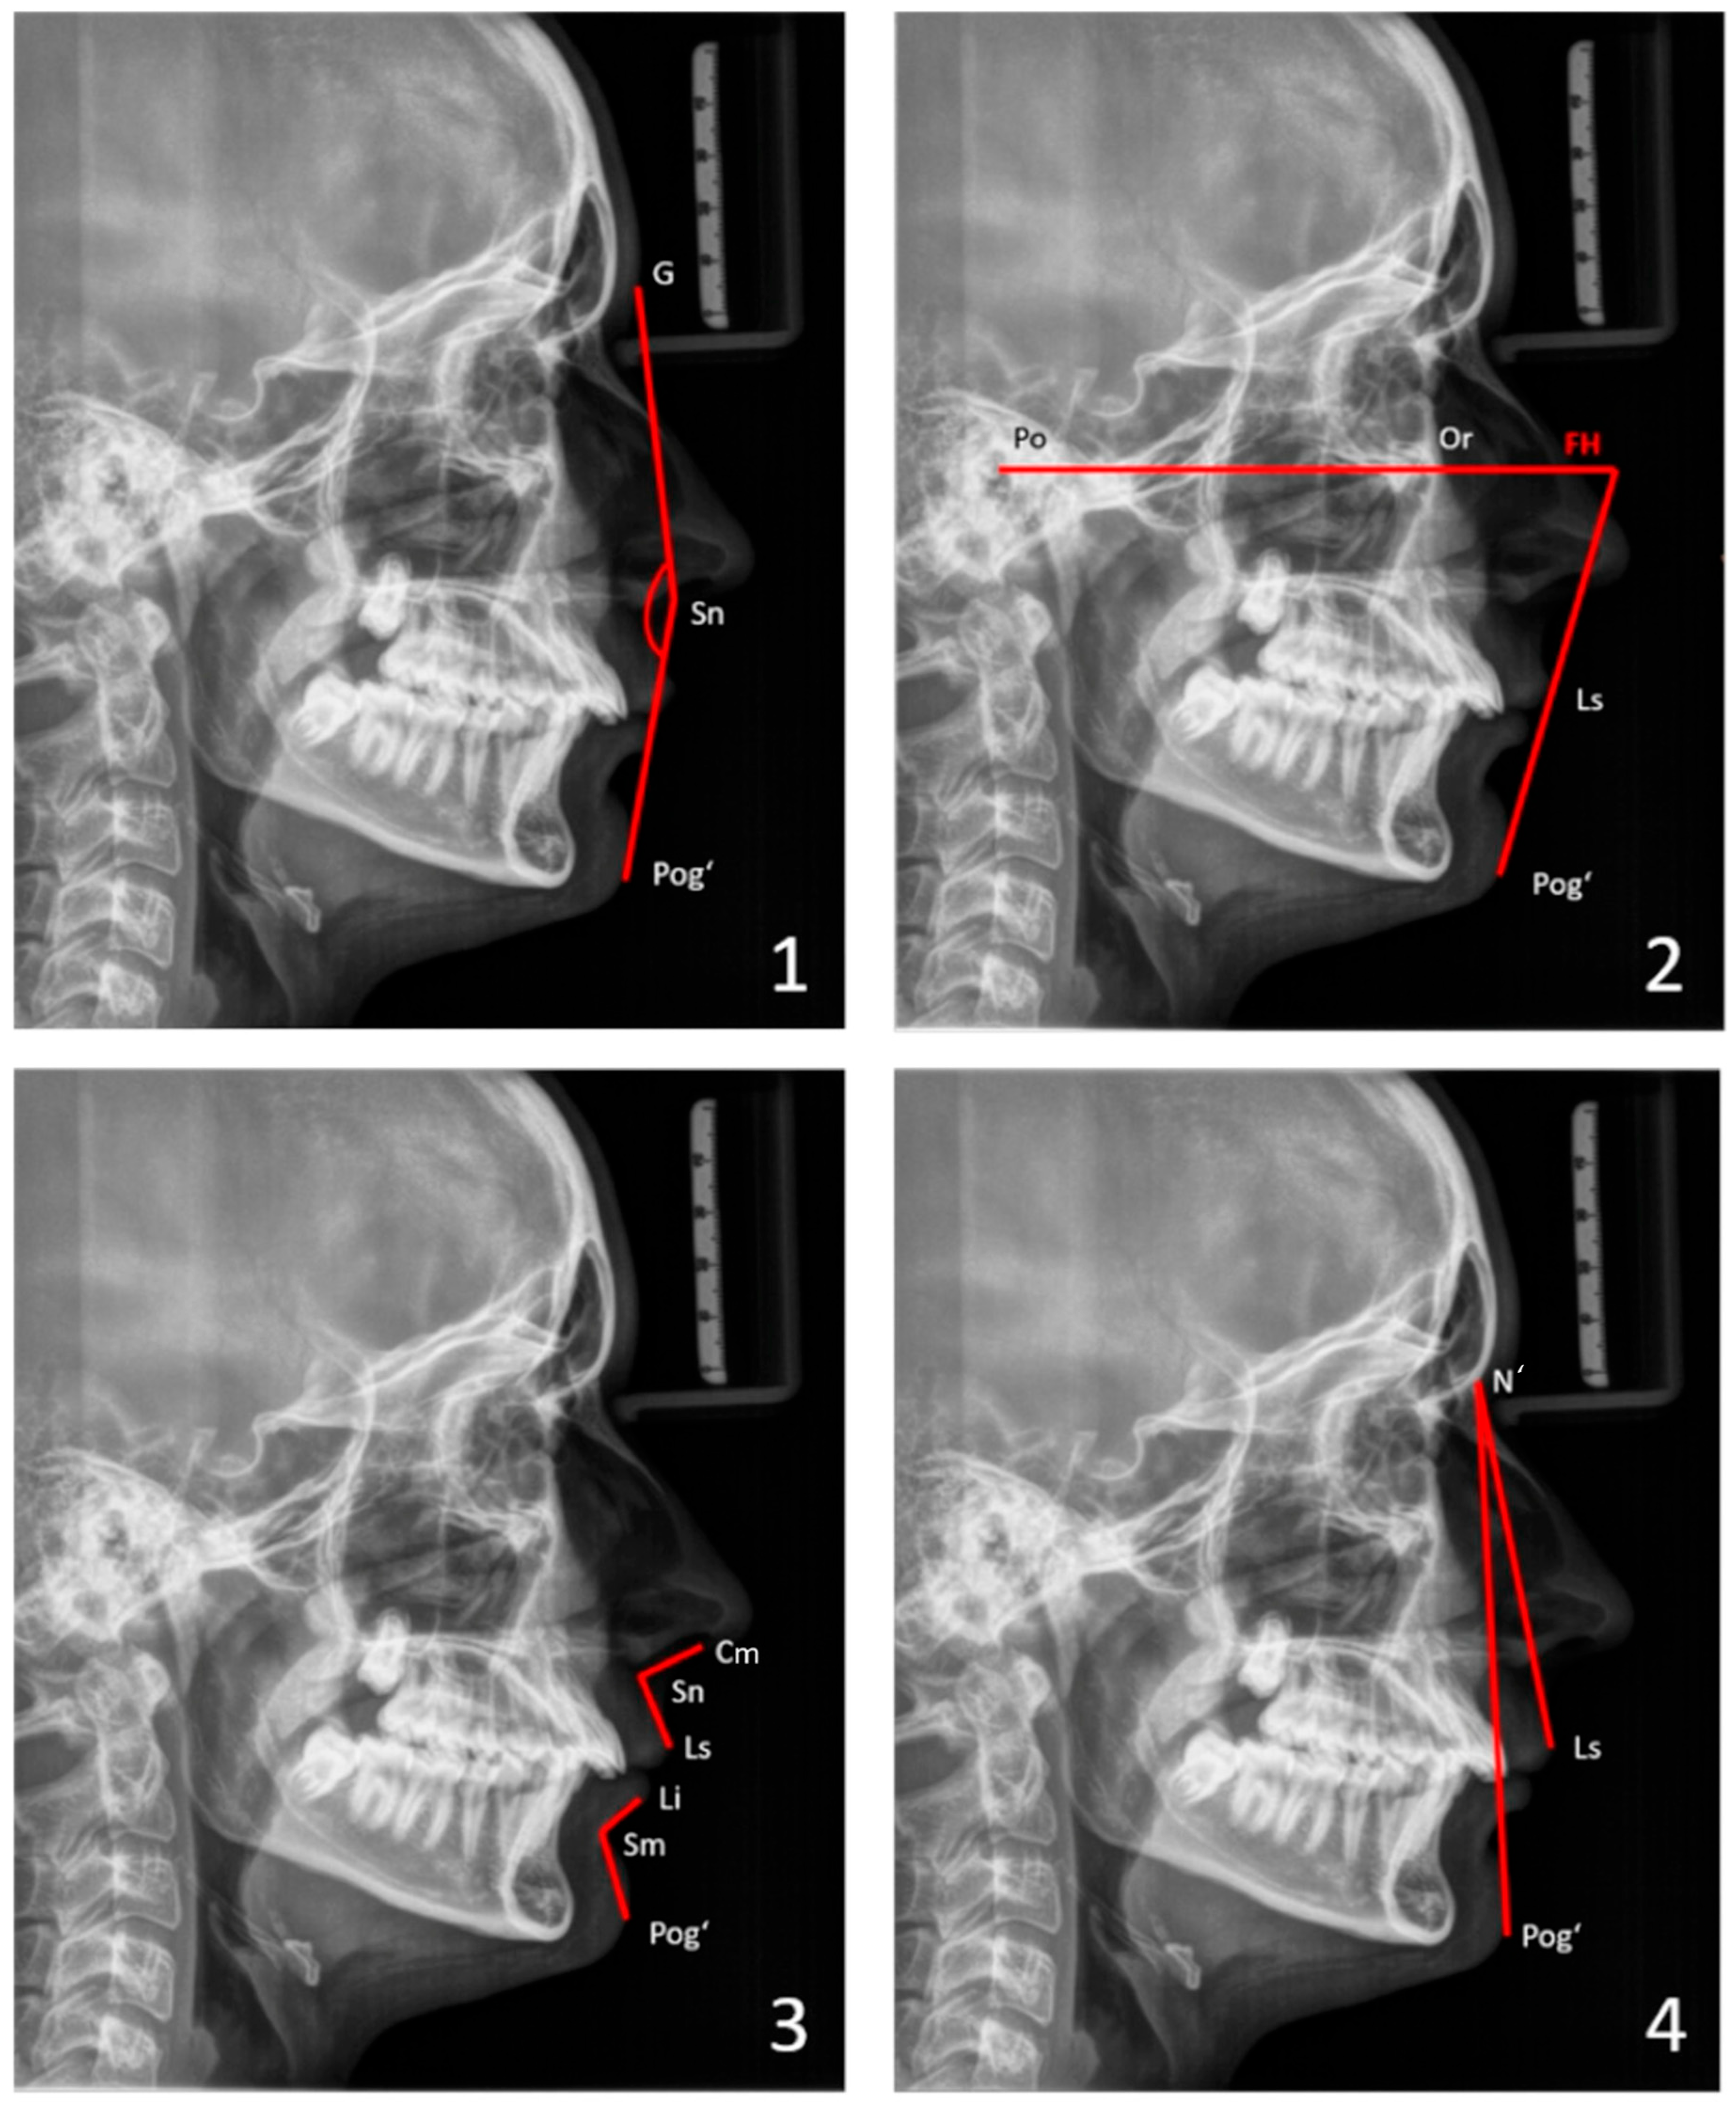

For soft-tissue cephalometric analysis, the facial profile was evaluated by an angular analysis. Facial convexity (GSnPog’), Z angle (the convexity of the lower facial profile, which is the intersection of FH and a line connecting the Pog’ and the most prominent lip), nasolabial angle (CmSnLs), mentolabial angle (LiSmPog’), and chin projection (LsN’Pog’) were considered (Figure 1). See the Appendix A for the definitions of landmarks and angles.

For the skeletal cephalometric analysis (a simplified analysis according to Tweed [35]), the sagittal positions of the maxilla (SNA) and the mandible (SNB) in relation to the cranial base, as well as their relative position to each other (ANB), were determined. Vertical parameters, such as the facial plane divergence (SN-GoGn angle), the FH plane–mandibular plane angle (FMA), and the gonial angle (CoGoMe), were considered to quantify the facial divergence (Figure 2). See the Appendix A for definitions of landmarks and angles.

For the architectural analysis according to Delaire, only cephalometric radiographs with a scale were used. Topographic analysis compared the areas of the five distinctive architectural territories of the facial skull (nasopremaxillary, maxillary, maxillary alveolar, ramus, and corpus of the mandible) to patient-specific optimal areas (patient-specific ideal norms). These territories are anatomically defined by four cranial lines (C1-C4) and eight craniofacial lines (CF1-CF8) [36,37] (Figure 3).

Mandibular size was assessed according to Suri et al. [25]. The following measures were taken: total mandibular length (Co-Gn), ramal length (Co-Go), body length (Go-Gn), and the ramal-to-body length ratio (Co-Go/Go-Gn) (see the Appendix A for definitions of landmarks). Mandibular sizes were evaluated in patients in two age groups: 11–13 years old (age 1; mean age: 11.7 years) and 14–18 years old (age 2; mean age: 15.6 years). These results were then compared to those of age-matched non-RS individuals from the normative cephalometric collection of Caucasian patients at the Burlington Facial Growth Research Center, Faculty of Dentistry, University of Toronto (mean age 1: 11.8 years; mean age 2: 16.6 years) [25] (Figure 4).

Mandibular width was determined by measuring the distance between the two antegonial notches on frontal cephalometric radiographs. Age-dependent reference values were used for this analysis (analysis according to Ricketts [38]) (Figure 5).